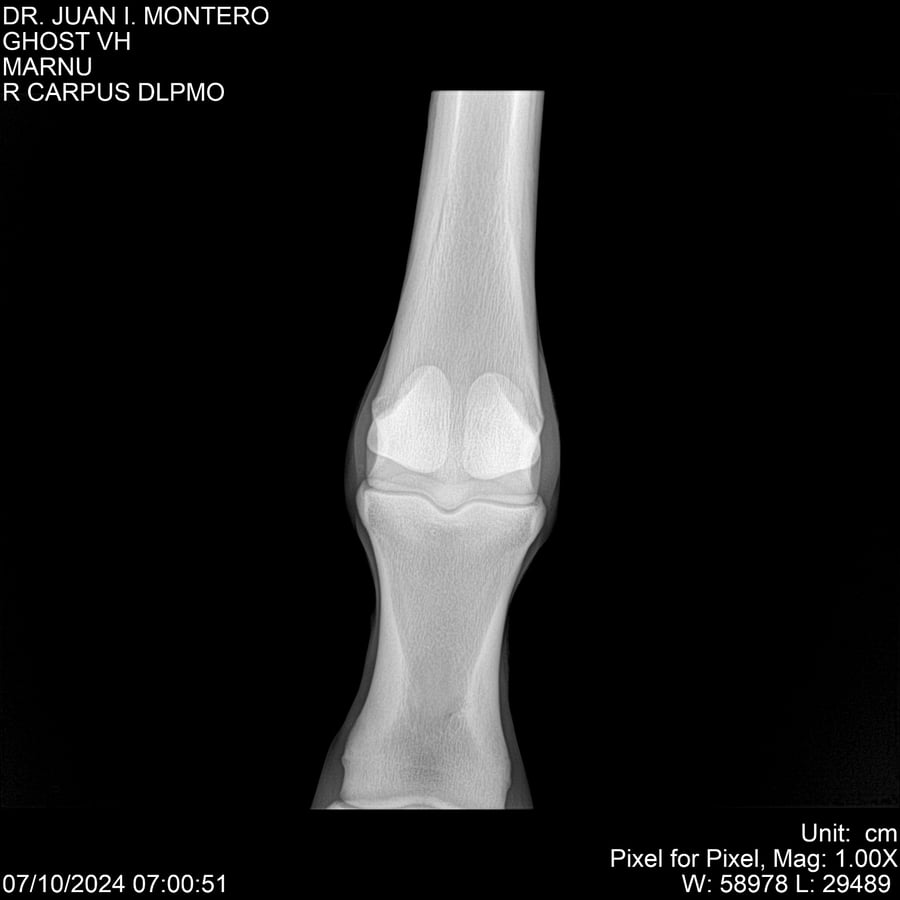

LOTE 15, GHOST VH 🔥 🔥 🔥 Lote Anterior Volver al remate Lote Siguiente Ficha Contacto Montevideo - Ficha del Lote Identificador: #282525 Categoría: Yeguarizos Montevideo - 69 Visualizaciones ClicData Contacto Empresa: Abelenda N. R., Walter Hugo Nombre*: Teléfono* : E-mail* : Mensaje Enviar Registrese gratis Este contenido Exclusivo está disponible sólo para usuarios registrados Ingresar